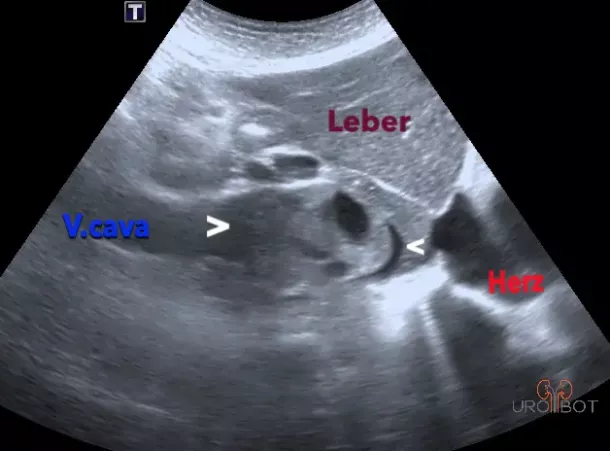

Tumorthrombus

Auf diesem Bild erkennt man einen großen Tumorthrombus in der unteren Hohlvene, ausgelöst von einem fortgeschrittenen Nierentumor

Video vom Tumorthrombus

Das Bild zeigt ein Video der Ultraschalluntersuchung des Tumorthrombus in der Vena cava.

Der Zugang zum Video erfolgt über die YouTube-Plattform.